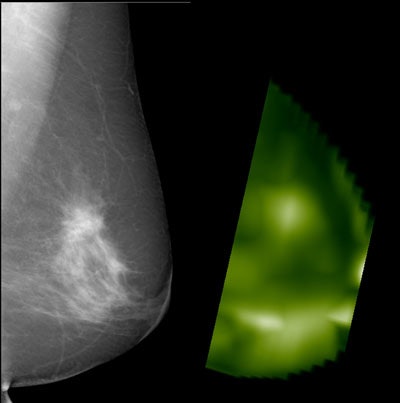

Mammography plus near-infrared breast imaging is slightly -- but not significantly -- more accurate than mammography alone when it comes to detecting breast lesions, German researchers found in a recent European Radiology study.

Poellinger and his team investigated the use of a commercially available, NIR imaging system (CTLM, Imaging Diagnostic Systems) as an adjunct to mammography in 276 consecutive patients. Four blinded readers assessed the images to identify a possible increase in diagnostic accuracy compared with mammography alone. There were 72 benign and 52 malignant lesions in the group of 124 lesions for which histologic proof was available.

The benefit of near-infrared breast imaging (NIBI) as an addition to mammography was determined by performing receiver operating characteristics (ROC) analyses for each reader based on BI-RADS categories and level of suspicion (LOS) scores.